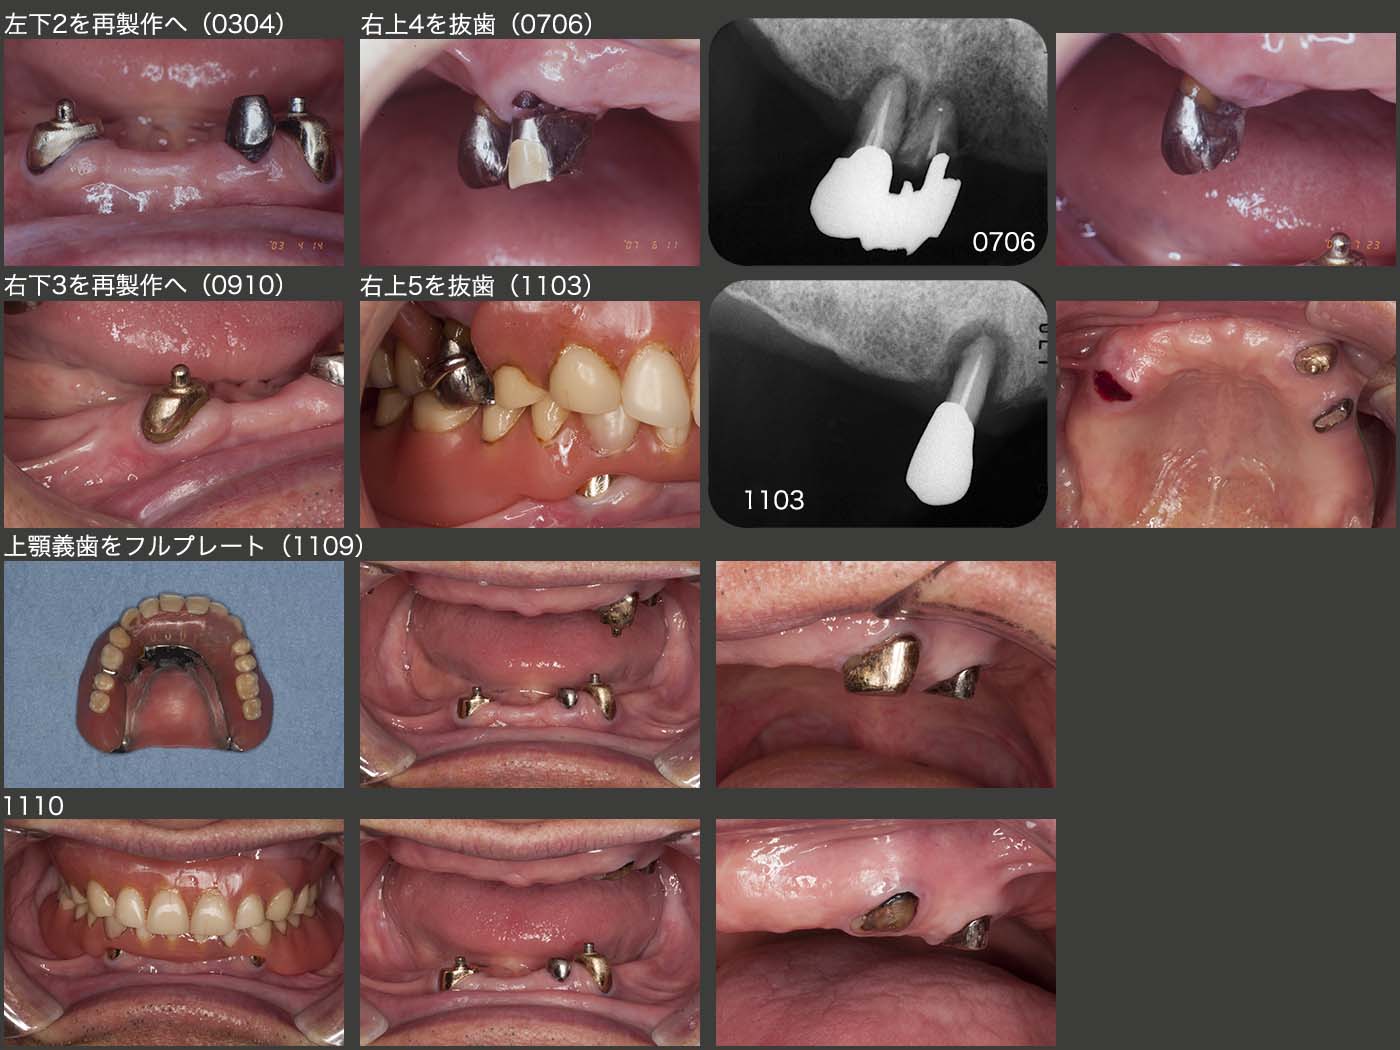

2003年4月,左下2の根面板を再製作した.07年6月には右上4に歯根破折が生じ,抜歯となった.対合が義歯にもかかわらず歯根破折が生じた例はあまり経験がない.09年10月,維持力回復のために右下3を再製作した.11年3月には,右上5を抜歯した.

上顎は右側に支台歯がなくなったため,左上3のアタッチメントによる維持力だけが頼りであるが,案の定,義歯の安定が十分に得られなくなってしまった.そこで11年9月,義歯床により口蓋を覆った.しかし,左上3が義歯の回転中心となり,同部の破損が何回か生じたため,メール部を除去し義歯床レジンの厚みを確保した.それでも同部の破損は収まらず,左上の2歯の抜去を考えた.しかし,患者さんの了解が得られなかった.そこで,左上3の根面板を除去し,出来る限り歯肉縁上歯質を削去し,義歯床レジンの厚みを確保した.11年10月,この状態で小康が得られた.